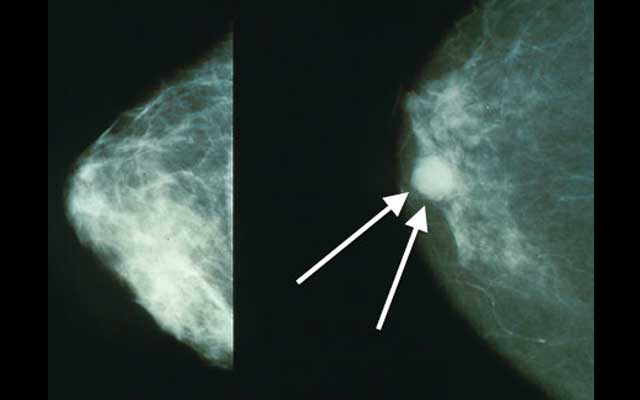

Image:wikimedia commons